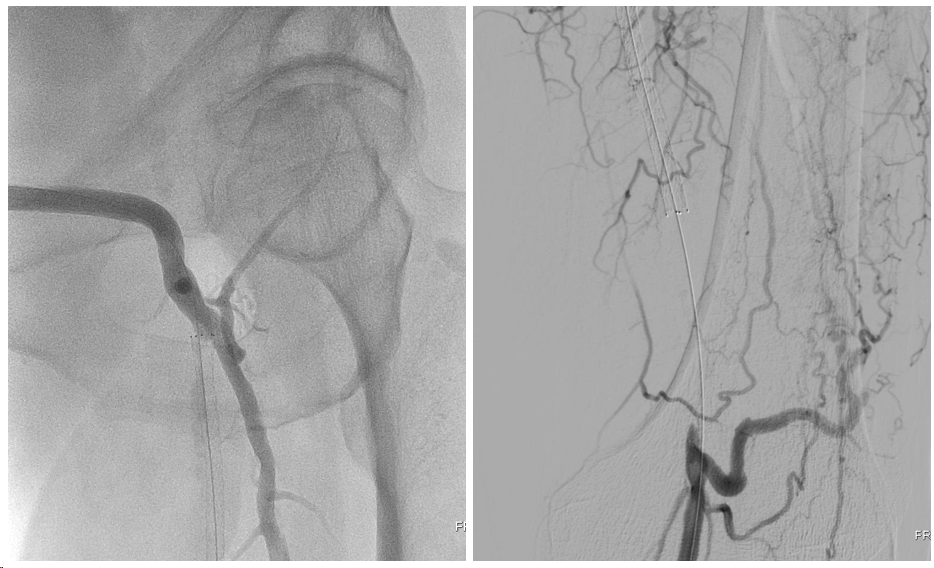

接着再次尝试顺行通过股深动脉病变,然而导丝始终无法顺利找到股深动脉开口,遂再次逆穿远端股深动脉,利用Command18导丝逆向通过股深动脉病变,自6F鞘中引出,自此,股动脉分叉病变顺利完成双导丝置入(图10)。

(图10)顺行开通股深动脉失败,逆穿远端股深动脉

首先选择治疗股深动脉病变,至少保证建立股总-股深-膝关节动脉网连续血流以恢复患肢血供。为了尽可能延长股深动脉的通畅时间,在4mm 、5mm Saber球囊预扩后,我们选择使用Resolute Integrity 冠脉药物涂层支架4*30mm覆盖股深动脉病变。接着,我们计划采用药物涂层球囊扩张股总-股浅动脉病变,在分别使用Orchid药物涂层球囊5.5*300mm、5.5*120mm扩张股浅动脉后,我们通过复查造影发现股浅动脉开口存在限流性夹层,为了确保金属裸支架释放过程中不会因为“前跳”现象而过度“出头”,我们选择了兼具极佳径向支撑力和释放精度的Smart Flex支架(5*150mm、5*120mm各一枚),利用Kissing Stent技术重建股动脉分叉,复查造影,股总-股浅及股总-股深均恢复连续血流(图11),术后3天患者顺利出院。

(图11)股深动脉DES+股浅动脉Smart Flex,利用Kissing Stent技术重建股动脉分叉